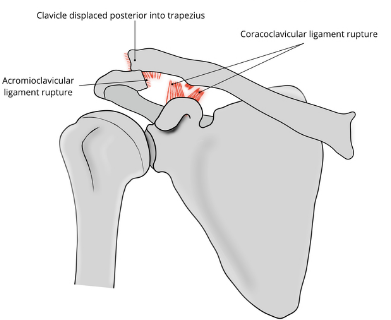

Based off Rockwood classification of acromioclavicular joint injury, what grade would this be?

4